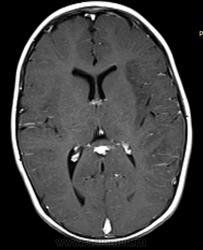

Ребенок 1 год 8 месяцев. В анамнезе с 06.12  многократные рвоты, повышение Т, слабость, сонливость, беспокойство, потиливость. БЫл поставлен диагноз ПТИ, после инфузионнйо терапии, дезинтоксикации в удовлетворительном состоянии выписана. Черезе месяц  гнойные высыпания на конечностях, диагноз пиодермия и дисфункция биллиарного тракта.  Полечили. Дальше в тчеении двух месяцев  однократные-многократные  рвоты, нарушение сна. Невропатолог поставил гидроцефальный синдрмо с тадии субкомпенсации. Ангиоретинопатия. На левой щеке на спине и на коже бедра гематомы в стадии отцветания. Сейчас состояние прогрессивно ухудшается.

Входящий диганоз пишут вирусный менингоэнцефалит. Рекомендуют диффреенцировать со свежими ишемическими изменениями и неопластическим процессом.

А что еще нужно? Диффузия есть, какой-то не очень понятный flair, зона изменений на них идентична Т2ВИ. По РКТ перед этим заподозрили арахноидальную кисту, диф с менингиомой задней трети серпа.

Учитывая возникающие мелкие гематомы на теле и ангиоретинопатию можно предпологать  некую патологию сосудистого русла.

В тоже время, ишемия (инсульт?) по времени (с июня 12г),а так же клиническим проявлениям не очень подходит.   Без отека, борозды сохранены, сдавление вон левого желудка...

Артериальный инфаркт в бассейн не умещается, тут и сма и пма. Синусы на взгляд проходимы. Так что мне кажется больше за энцефалит. Оболочки правда не утолщены (если менингоэнцефалит).

Анамнез не дочитал сначала. За опухоль на мой взгляд данных нет вообще. Изменения идут по коре на большом протяжении с небольшой относительно зоной отёка белого вещества. Так что менингоэнцефалит наиболее вероятен. Анамнез ликвора на мой взгляд обязателен, хотя я и не невролог.

Масс-эффект есть - присмотритесь к бороздам на Т1. Есть поражение и коры, и белого вещества - такое бывает при нарушении кровотока по мелким сосудам. Снижение диффузии (я так понимаю, ADC снижен?) как раз говорит о цитотоксическом отеке и характерно для инфаркта. Единственное, что смущает - это вовлечение бассейна ПМА. Но, во первых, эти бассейны у людей вариабельны, и вполне может оказаться, что медиальные отделы полушария кровоснабжаются у этого пациента из СМА. А во-вторых, если есть патология сосудов, то почему бы и не поражение 2 бассейнов сразу? Так что, я не вижу тут ничего, что бы не укладывалось в инсульт. А посему пользуемся бритвой Оккама.

Энцефалит как правило двусторонний. Все эти болезни обмена - тоже множественные участки.